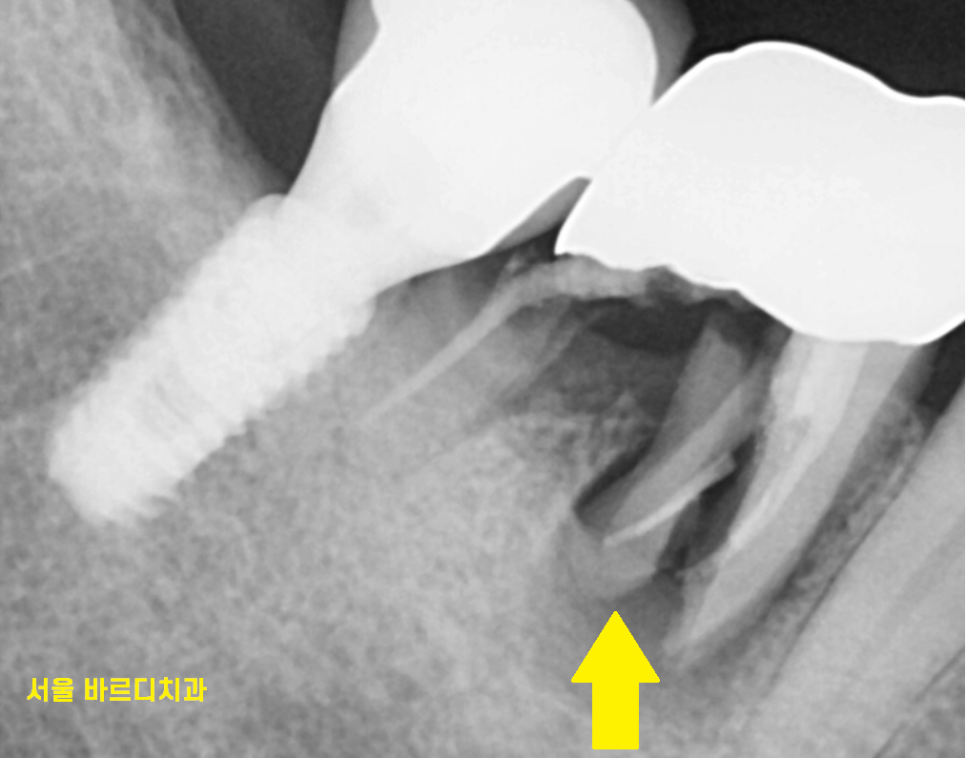

치아 뿌리 균열을 넘어

바스러졌습니다.

이건 망치로 내려친듯

완전히 치아뿌리가 산산 조각이 나서

뽑을 수 밖에 없었는데요.

치아 뿌리 균열 상태에 비하여

뼈는 나쁘지 않아서

치아 뿌리 균열이 하루 이틀 있던 일이 아니라

잇몸뼈가 부분적으로 녹은 부분이 있었습니다.